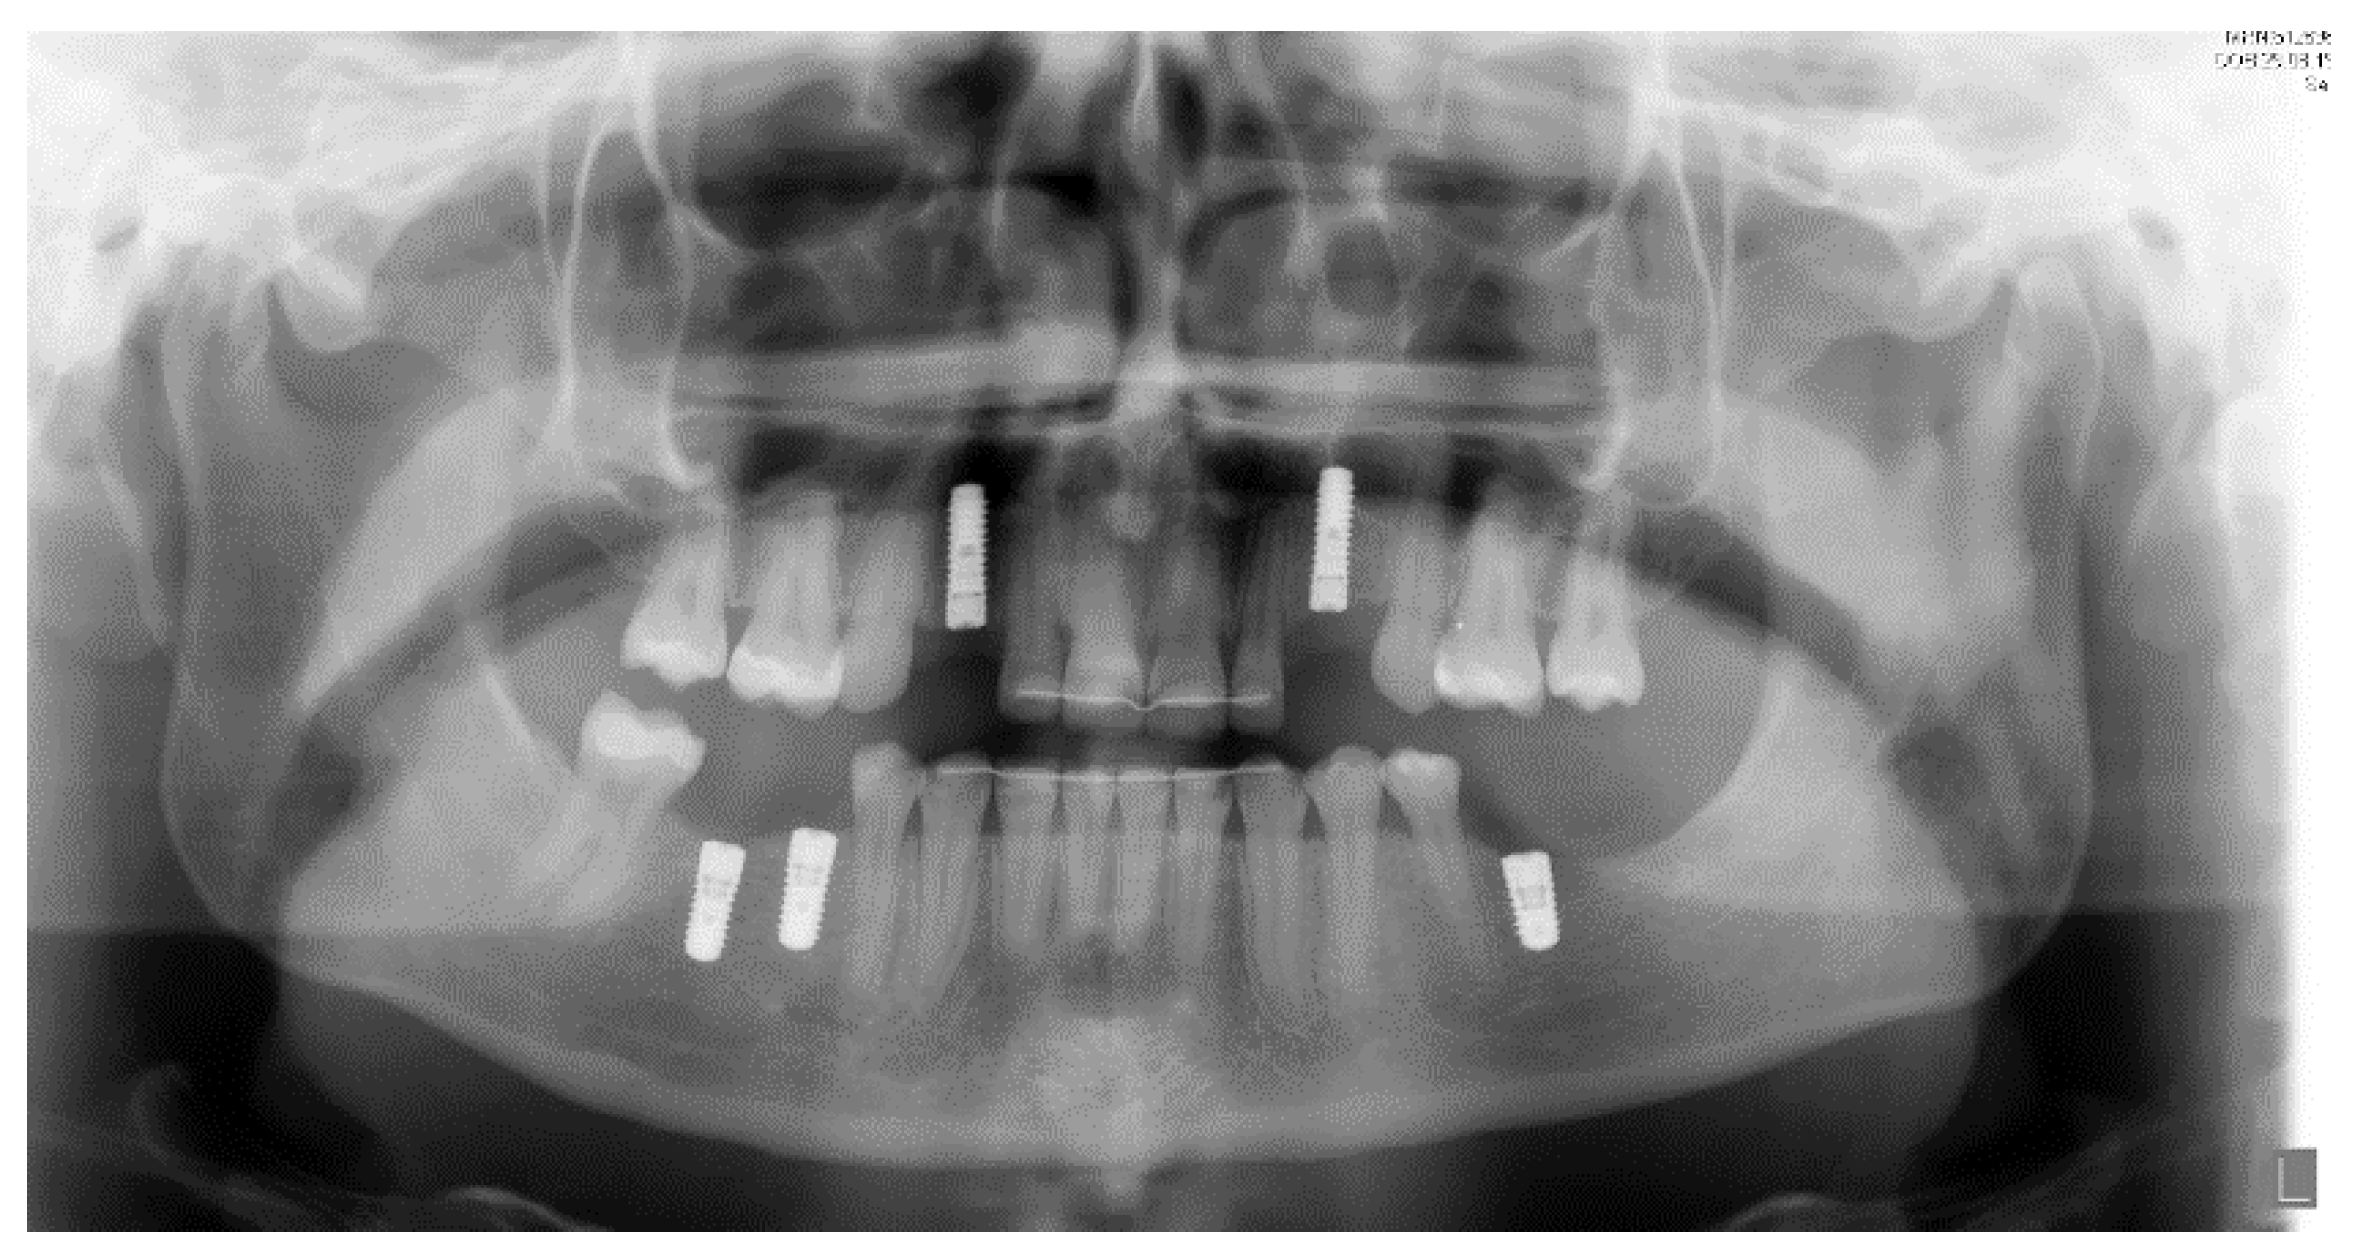

2.1. Case One

2.2. Case 2